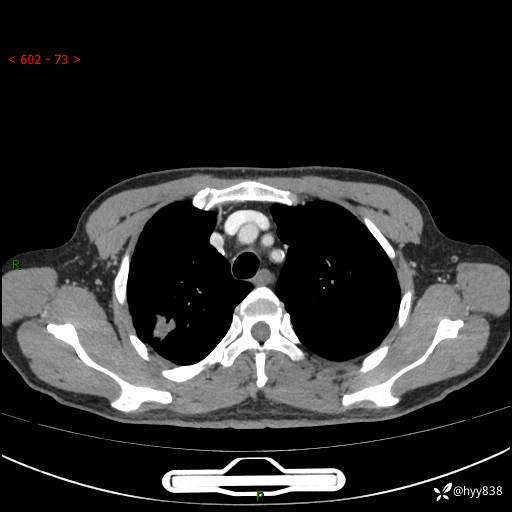

69岁/男,发现肺部病变6天。该有的征象都有,肉芽肿 VS 肿瘤,一念之间---(有结果)

主诉:发现肺部病变6天。

现病史:患者6天前于我院泌尿外科住院,住院期间行胸部CT检查,提示“肺部病变”,患者无畏寒、发热、盗汗、咳嗽、咳痰、咯血、胸痛、呼吸困难,无反酸、腹痛、腹泻、头痛、头晕等不适。未予特殊处理,现为进一步诊治,门诊以“肺肿物”收入我科。 患者本次起病以来,精神食欲尚可,大小便正常,体力及体重无明显变化。

胸部CT平扫+增强